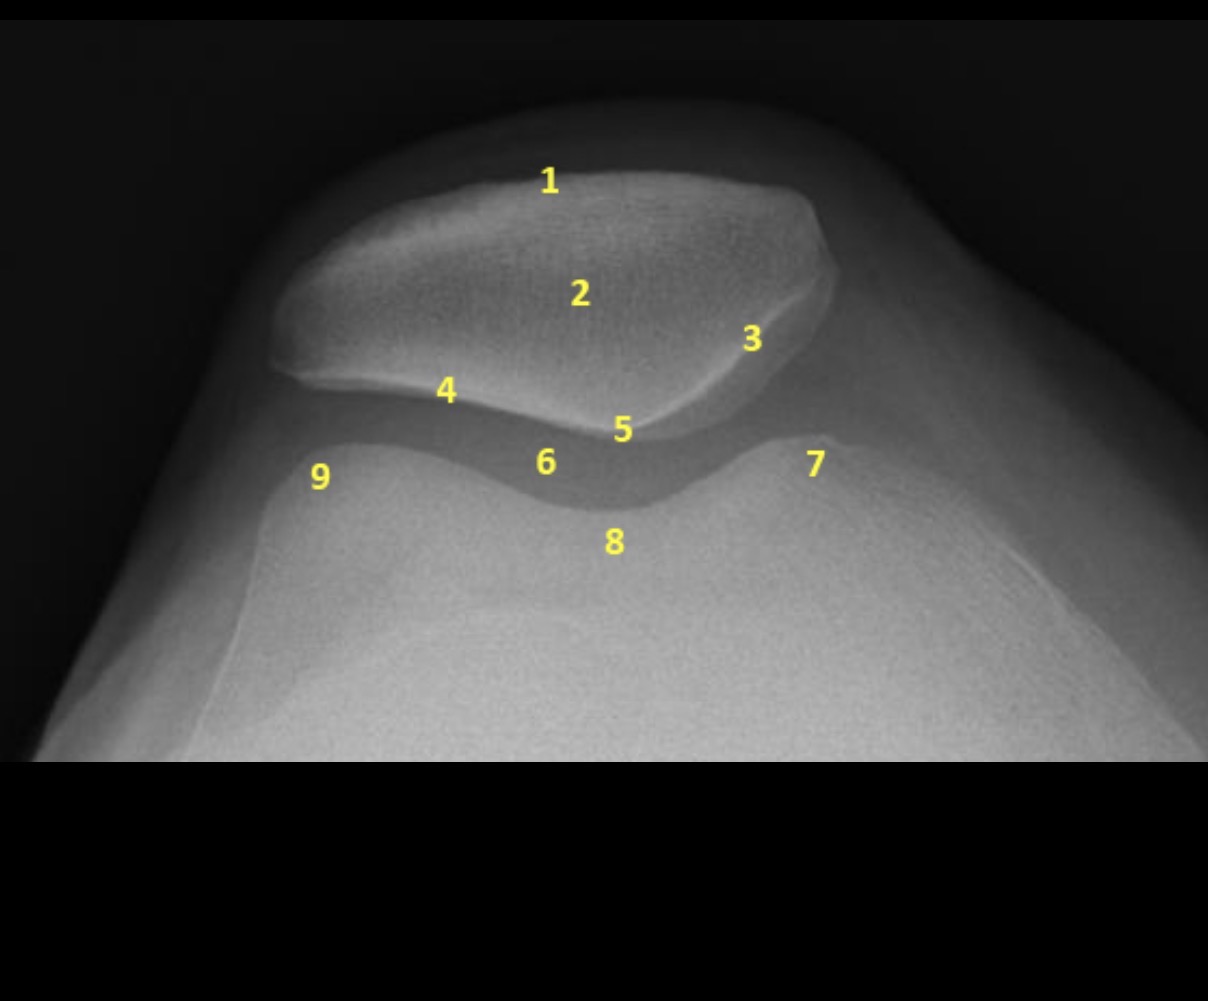

Name the projection.

Should it be repeated, if so why?

Settegast Method or Sunrise View

No.

Label the image.

External cortical surface of patella (not needed for practical)

Patella

Medial facet of patella

Lateral facet of patella

Median patellar ridge

Femoropatellar joint

Medial trochlear ridge

Trochlear groove

Lateral trochlear ridge